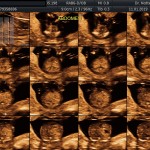

- Los Marcadores Cromosómicos y determinación de riesgo para trisomías (Rastreo de S. Down y otros con una sensibilidad del 65% aprox.).